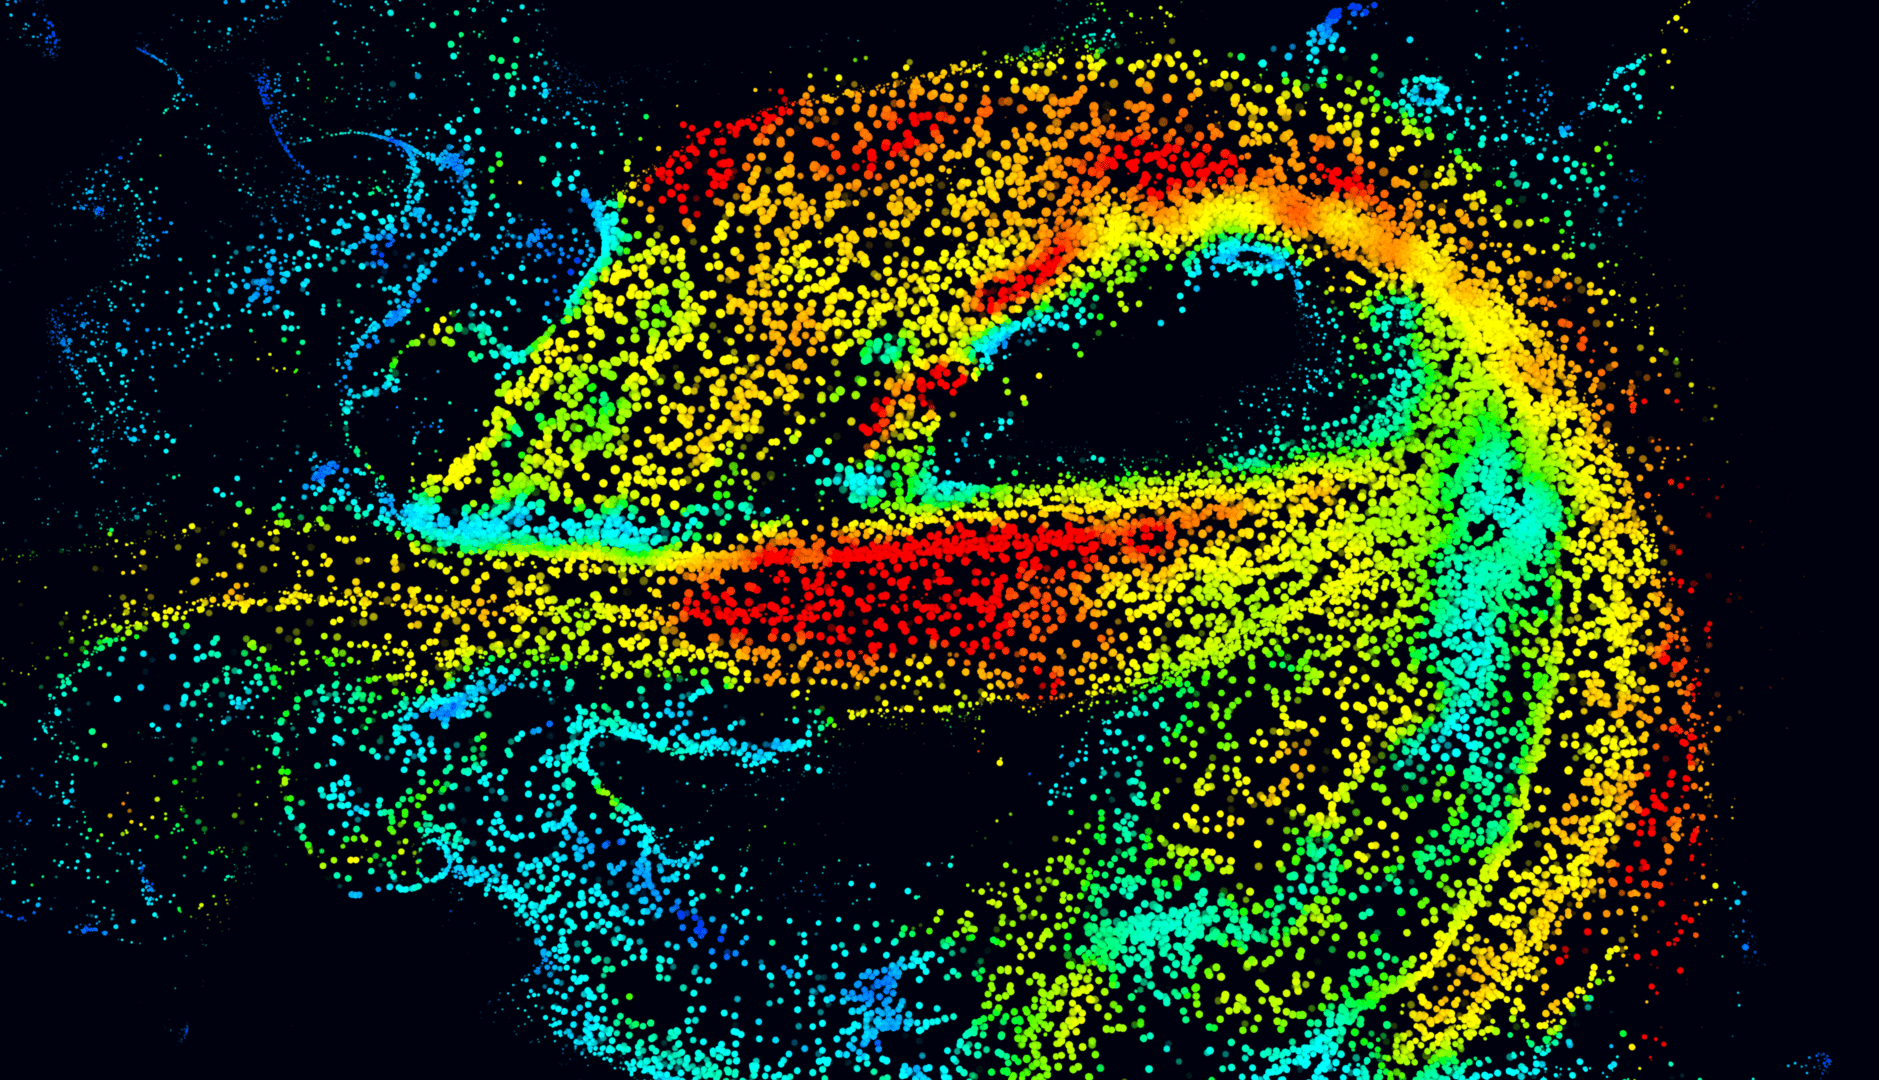

This is now possible in the adult human brain at microscopic resolution using ultrasound localization microscopy (ULM) of intravenously injected microbubbles. To take advantage of this concept, we’re developing a transcranial ULM scanner for stroke and aneurysm diagnosis in adults, in close collaboration with Geneva University and Physics for Medicine Paris.

This is a ‘moonshot’ project that is focused on developing a highly temporally-resolved version of our existing ultrafast localization microscopy (ULM) technology for Iconeus One. In this clinical proof-of-concept project, we are initially aiming to achieve diagnosis and treatment monitoring of cerebral small vessel disease, stroke, aneurysms, and alterations of the neurovascular response.

To reduce the temporal resolution from the current 60 s to the <1 s needed for this ‘functional ULM’ (fULM) technology, we’re planning to use a set of highly sensitive ultrasound probes within a helmet. This will present significant challenges, but in conjunction with our collaborators in the EU-funded MICROVASC project, we’re confident about making progress, and are looking forward to seeing what can be achieved for clinical applications.